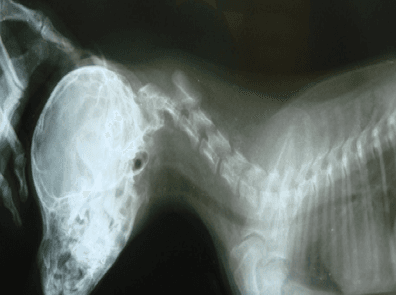

На рентгене у животного с атланто-аксиальной нестабильностью наблюдается увеличение пространства между гребнем первого шейного позвонка и дорсальной (верхней) дугой атланта. Снимки выполняются в боковой проекции, голова животного должна быть согнута в шейном отделе (т.н. “стресс-снимок”). Проведение исследования требует аккуратности, так как сильное сгибание шеи может привести к усугублению симптоматики.